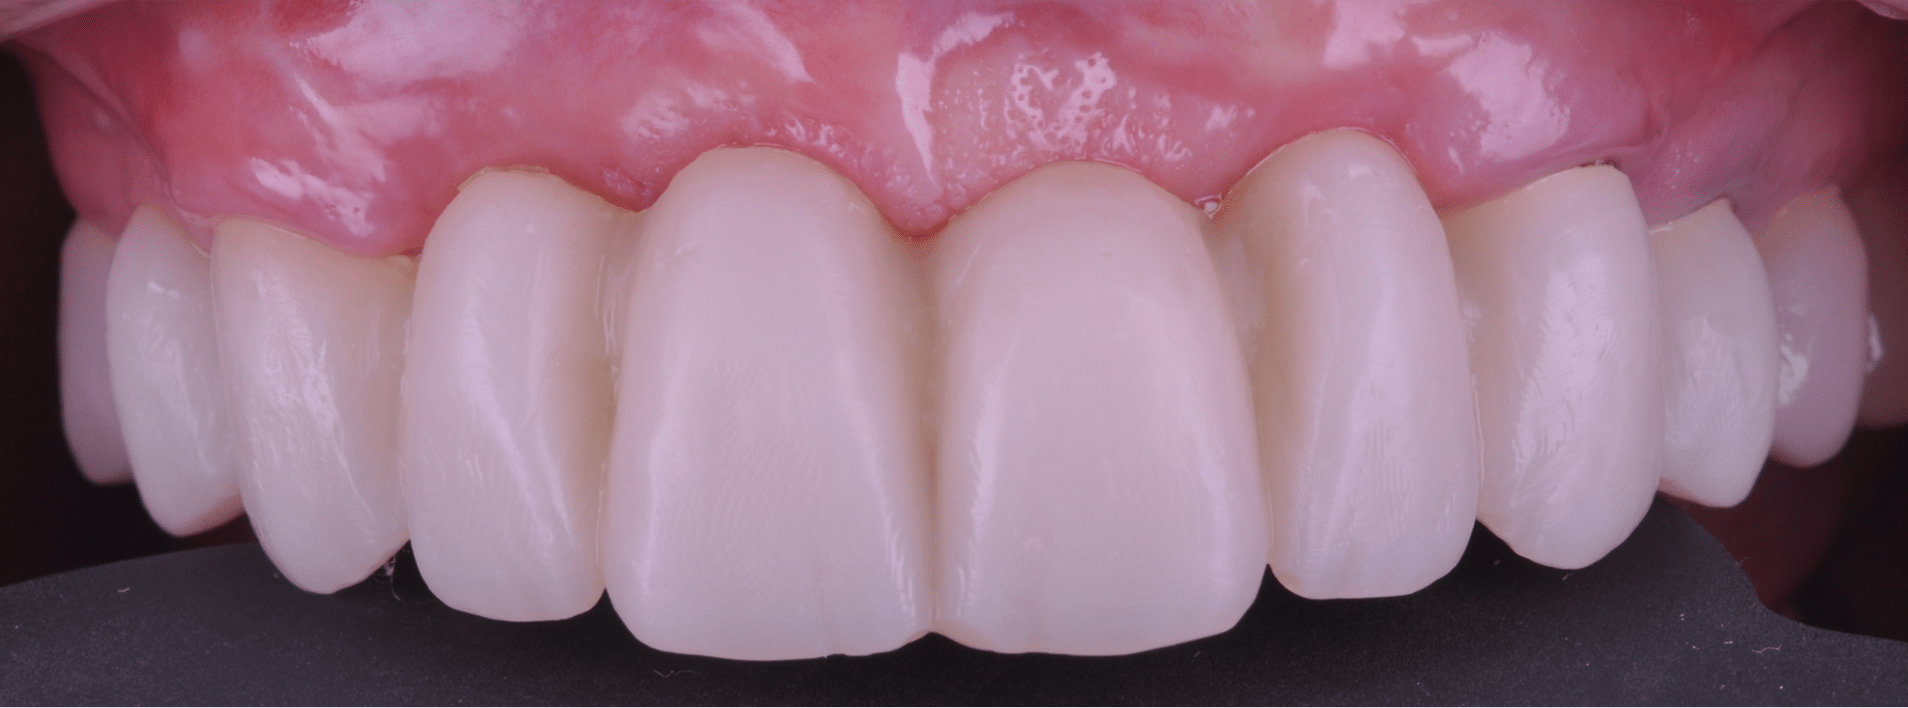

Doar astfel putem crea profilul de emergență corect al coroanei dentare, ceea ce permite conformarea papilei și a sulcusului.